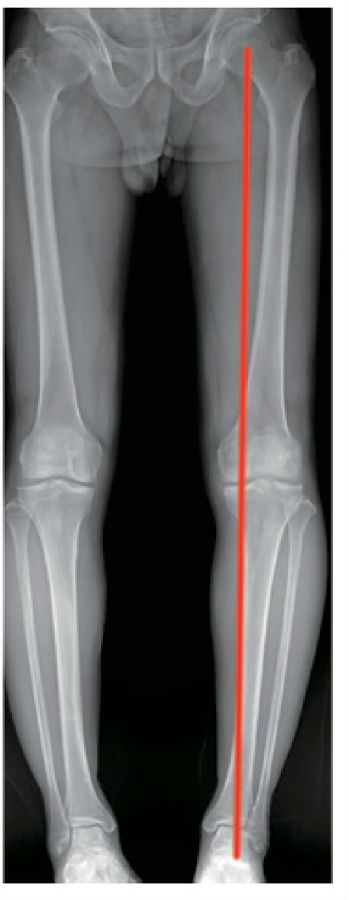

典型病例为一64岁男性患者,左膝关节疼痛2年并加重半年。查体见左膝内翻畸形,内侧关节间隙压痛,膝关节活动度无明显异常,X线片示左膝关节骨关节炎,内侧间室狭窄,K-L分级3级。诊断为左膝关节骨关节炎,合并内翻畸形。行PSI导板辅助下左胫骨内侧高位截骨术,术后第2天开始患肢部分负重,术后8周开始完全负重。术后3个月影像学检查示下肢力线矫正满意,截骨已愈合,左膝内侧间隙较术前增宽,术后3个月复查患者负重行走无疼痛,功能恢复满意。手术前后影像学资料见图4~7。

图4 术前双下肢全长X线片示左膝内翻畸形

图6 术后3个月双下肢全长X线片示力线矫正满意